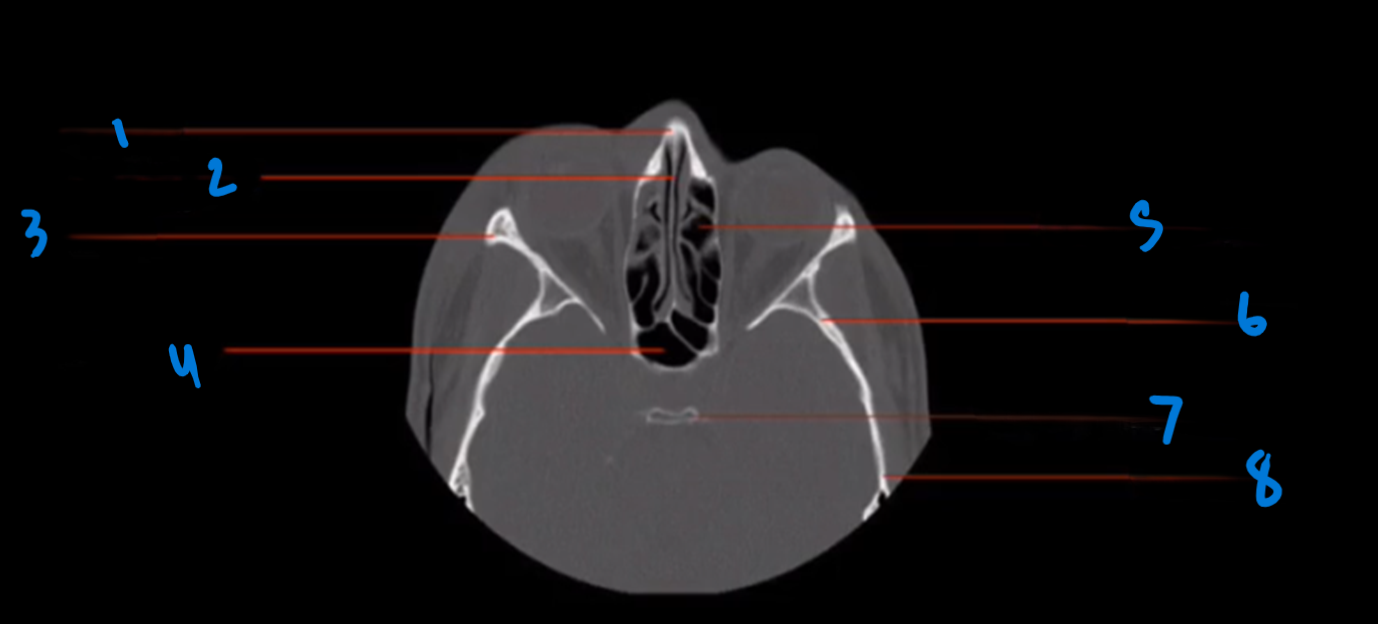

What is landmark #1 called?

Nasal bone

What is landmark #2 called?

Perpendicular plate, ethmoid bone

What is landmark # 3 called?

Zygoma

What is landmark # 4 called?

Sphenoid Sinus

What is landmark # 5 called?

Ethmoid air cells (sinus)

What is landmark # 6 called?

Sphenoid bone

What is landmark # 7 called?

Dorsum Sellae, sphenoid bone

What is landmark # 8 called?

Temporal Bone